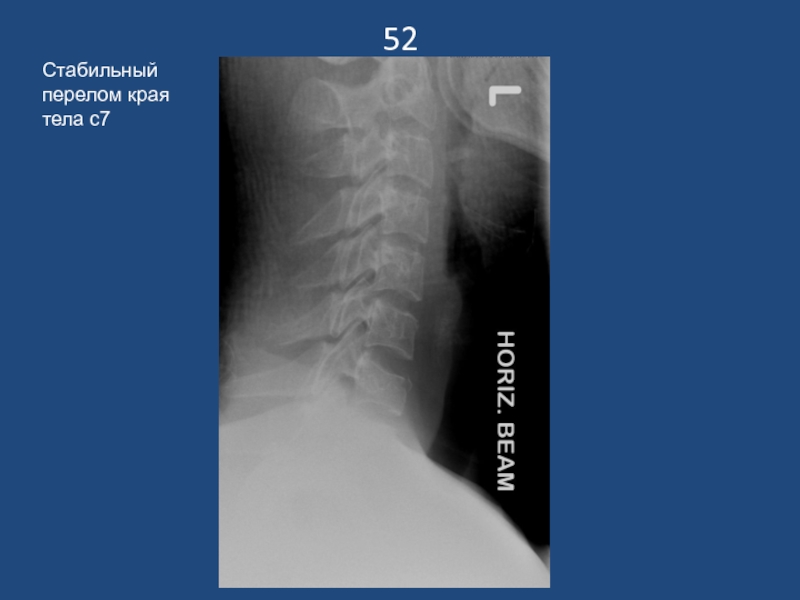

Слайд 5352

Стабильный перелом края тела с7

52Стабильный перелом края тела с7